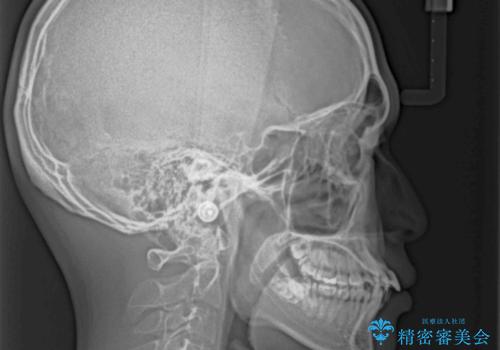

口元はやや突出感があったため、上下左右の第一小臼歯4本を抜歯してワイヤー矯正にて抜歯矯正を行うこととしました。

また、左右ともに最後臼歯が交叉咬合になっており、外側に飛び出している上顎の最後臼歯を補助装置を利用して、積極的に内側に引き込むようにしました。